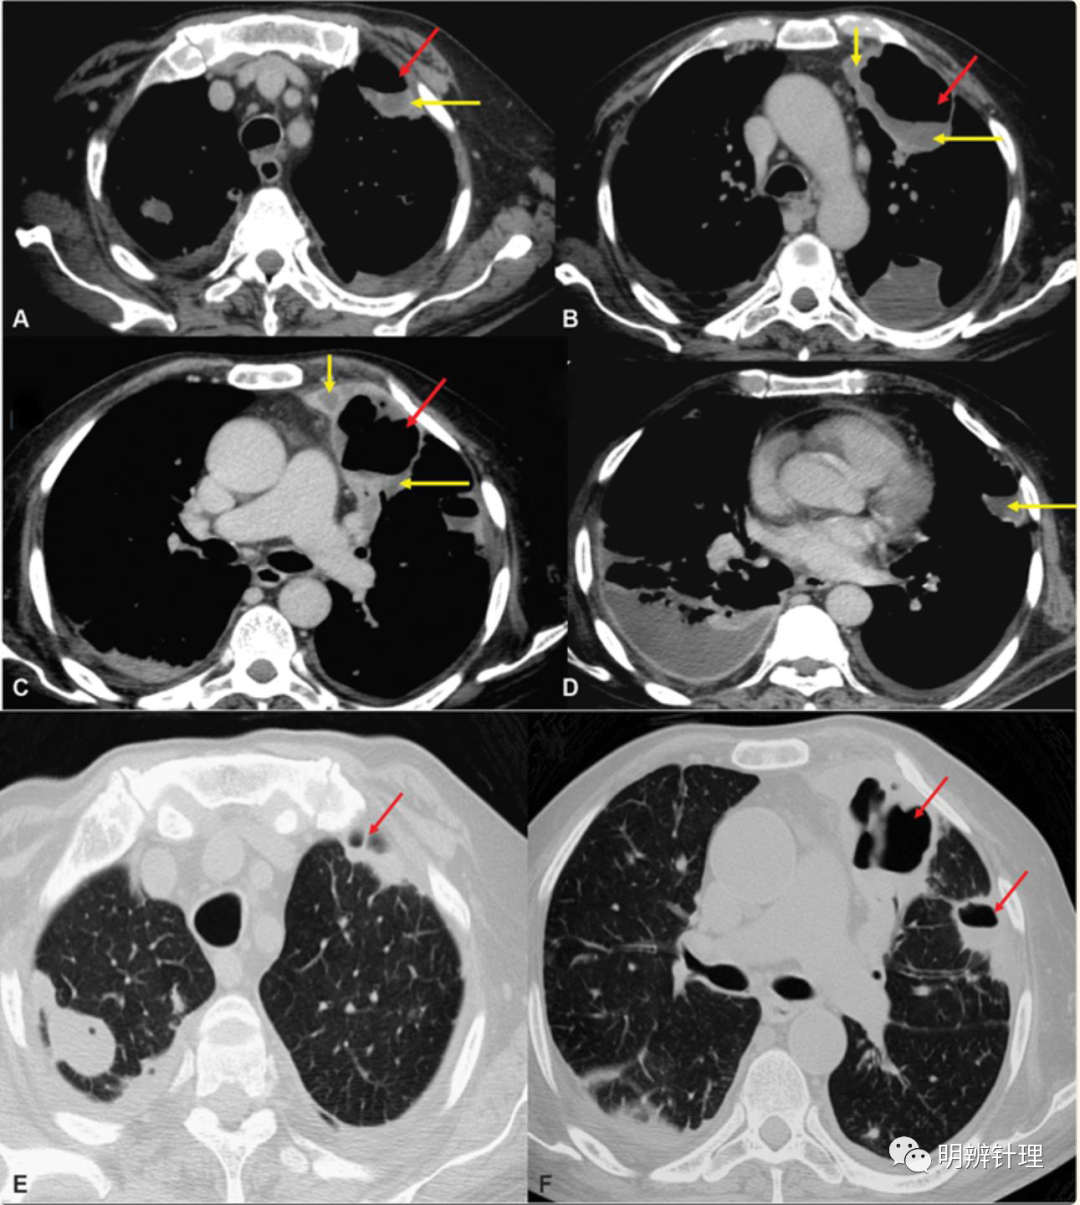

男性,57岁,咳嗽、发烧和呼吸窘迫2周,糖尿病病史控制不佳。增强CT ( A–D ) 显示多段坏死性实变(红色箭头),低强化肺实质(黄色箭头)。双侧脓胸。肺窗( E、F )显示肺实变伴空洞(红色箭头)。

诊断结果:血培养链球菌和葡萄球菌